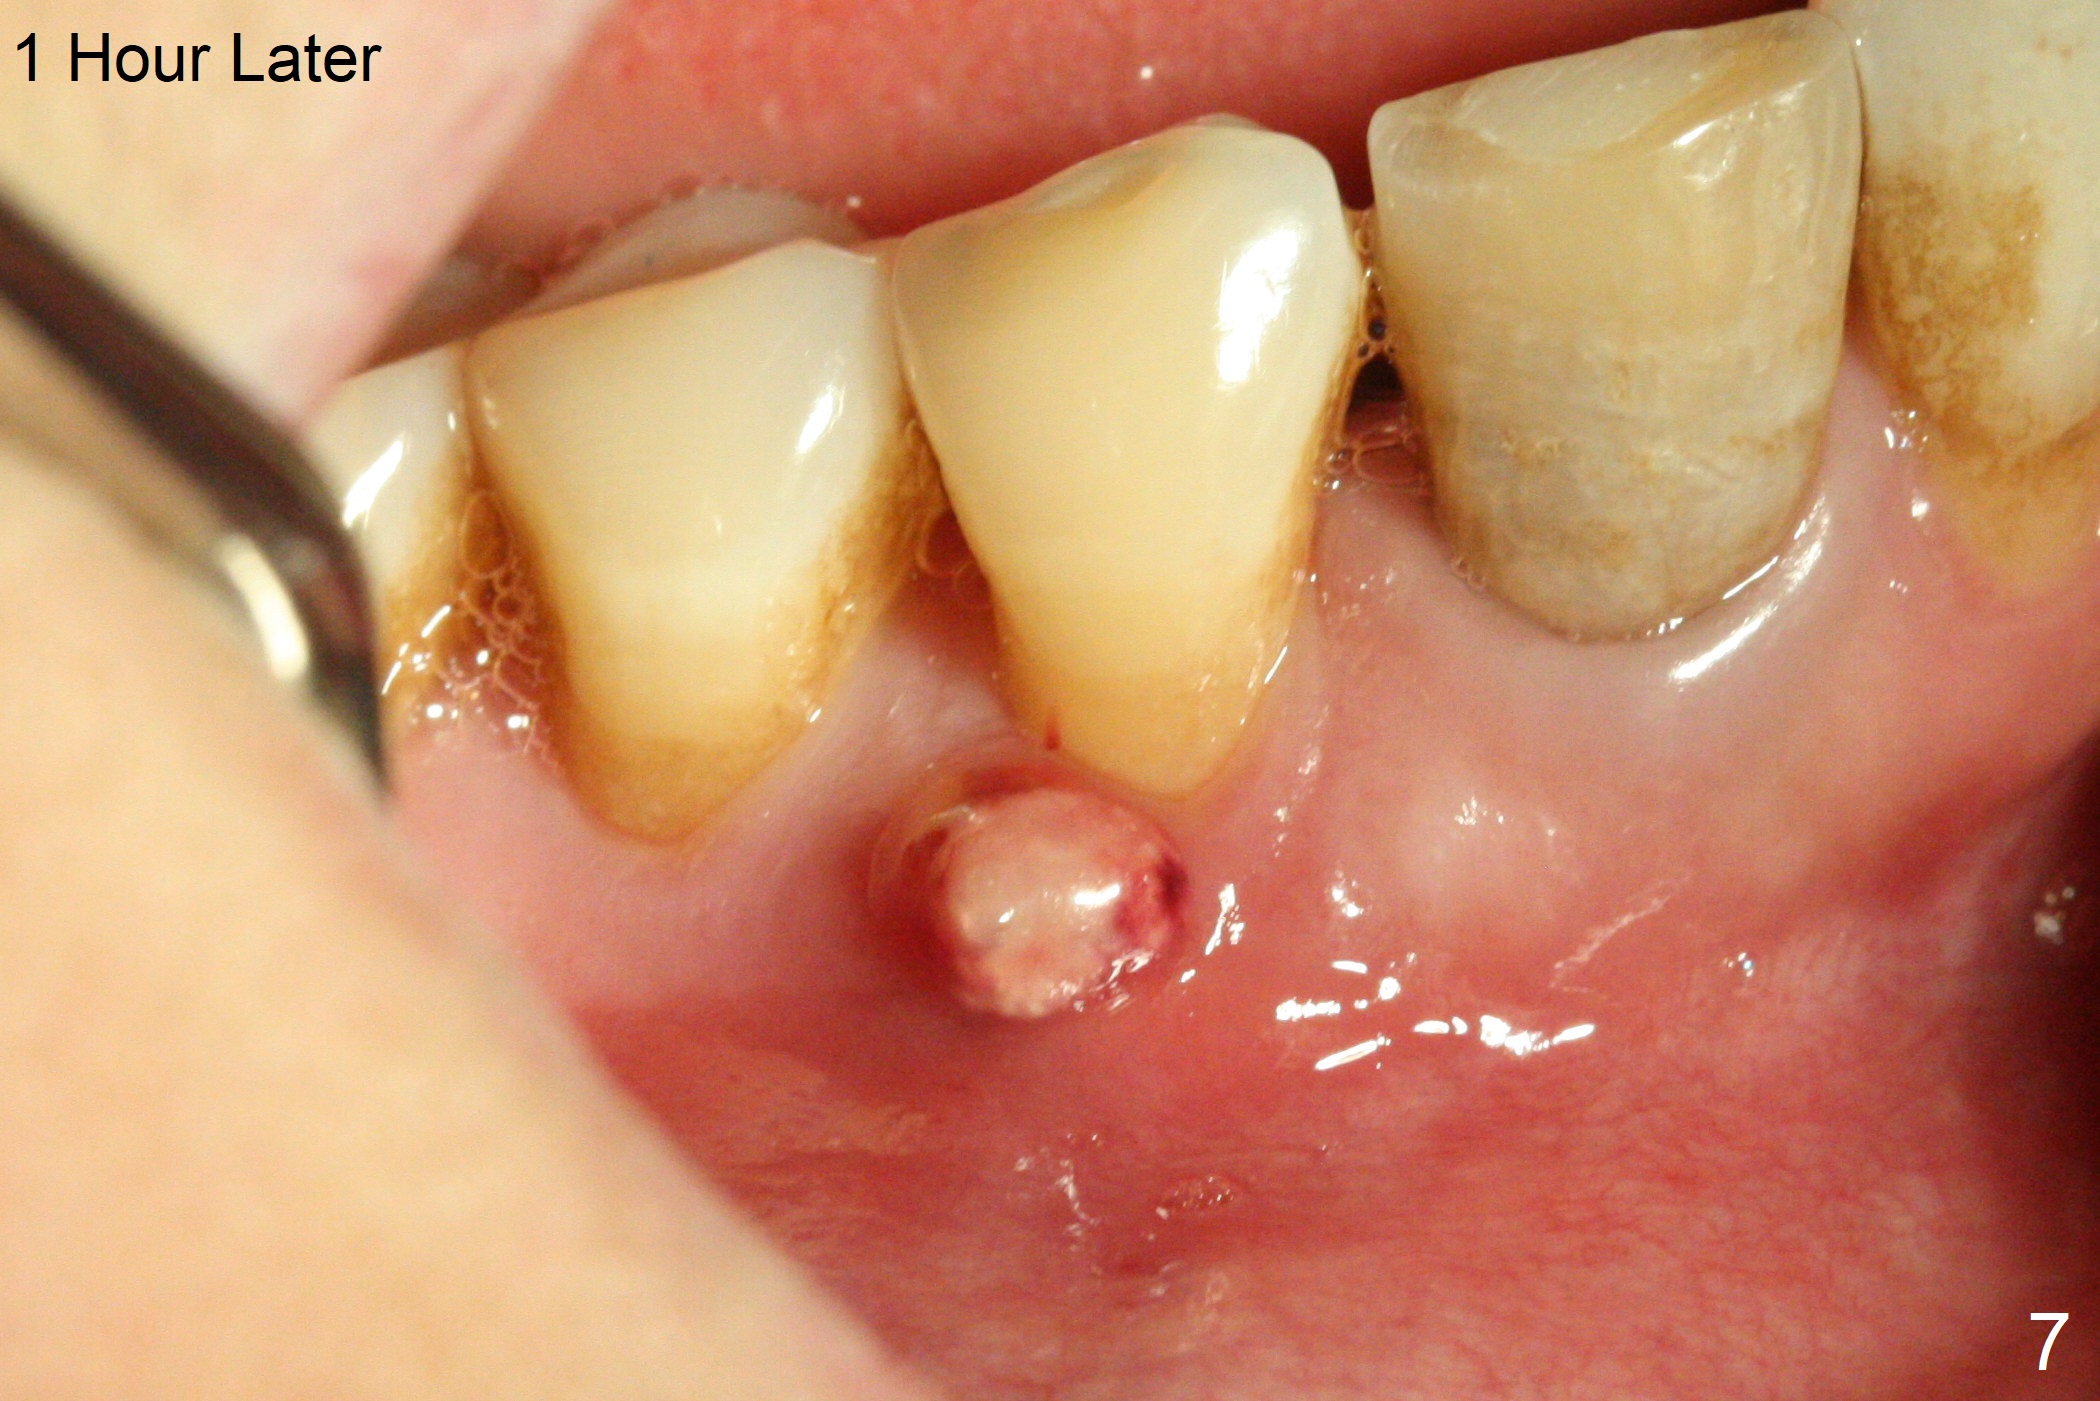

The patient reports that the fistula disappears after initial RCT at #27, but it seems to re-appear 1 month post canal debridement (Fig.5 >). After repeated debridement with #40 hand file at 23 mm, apply Endo Sequence BioCeramic Sealer and insert GT 40/.08 master cone with black carrier (Fig.6). One hour later, the patient returns with re-appearance of the fistula (Fig.7). Following local anesthesia, poking the fistula leads to sealer escape (Fig.8). After debridement of the fistula until the bone, PA is retaken (Fig.9). A crown was made in China; mesial radiolucency starts (Fig.10). The tooth remains asymptomatic 1 year 5 months postop (Fig.11). There is a lingual fistula with enlarged mesial radiolucency 2 years 3 months postop (Fig.12-14).